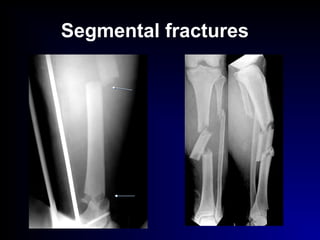

 segmental

Segmental fractures